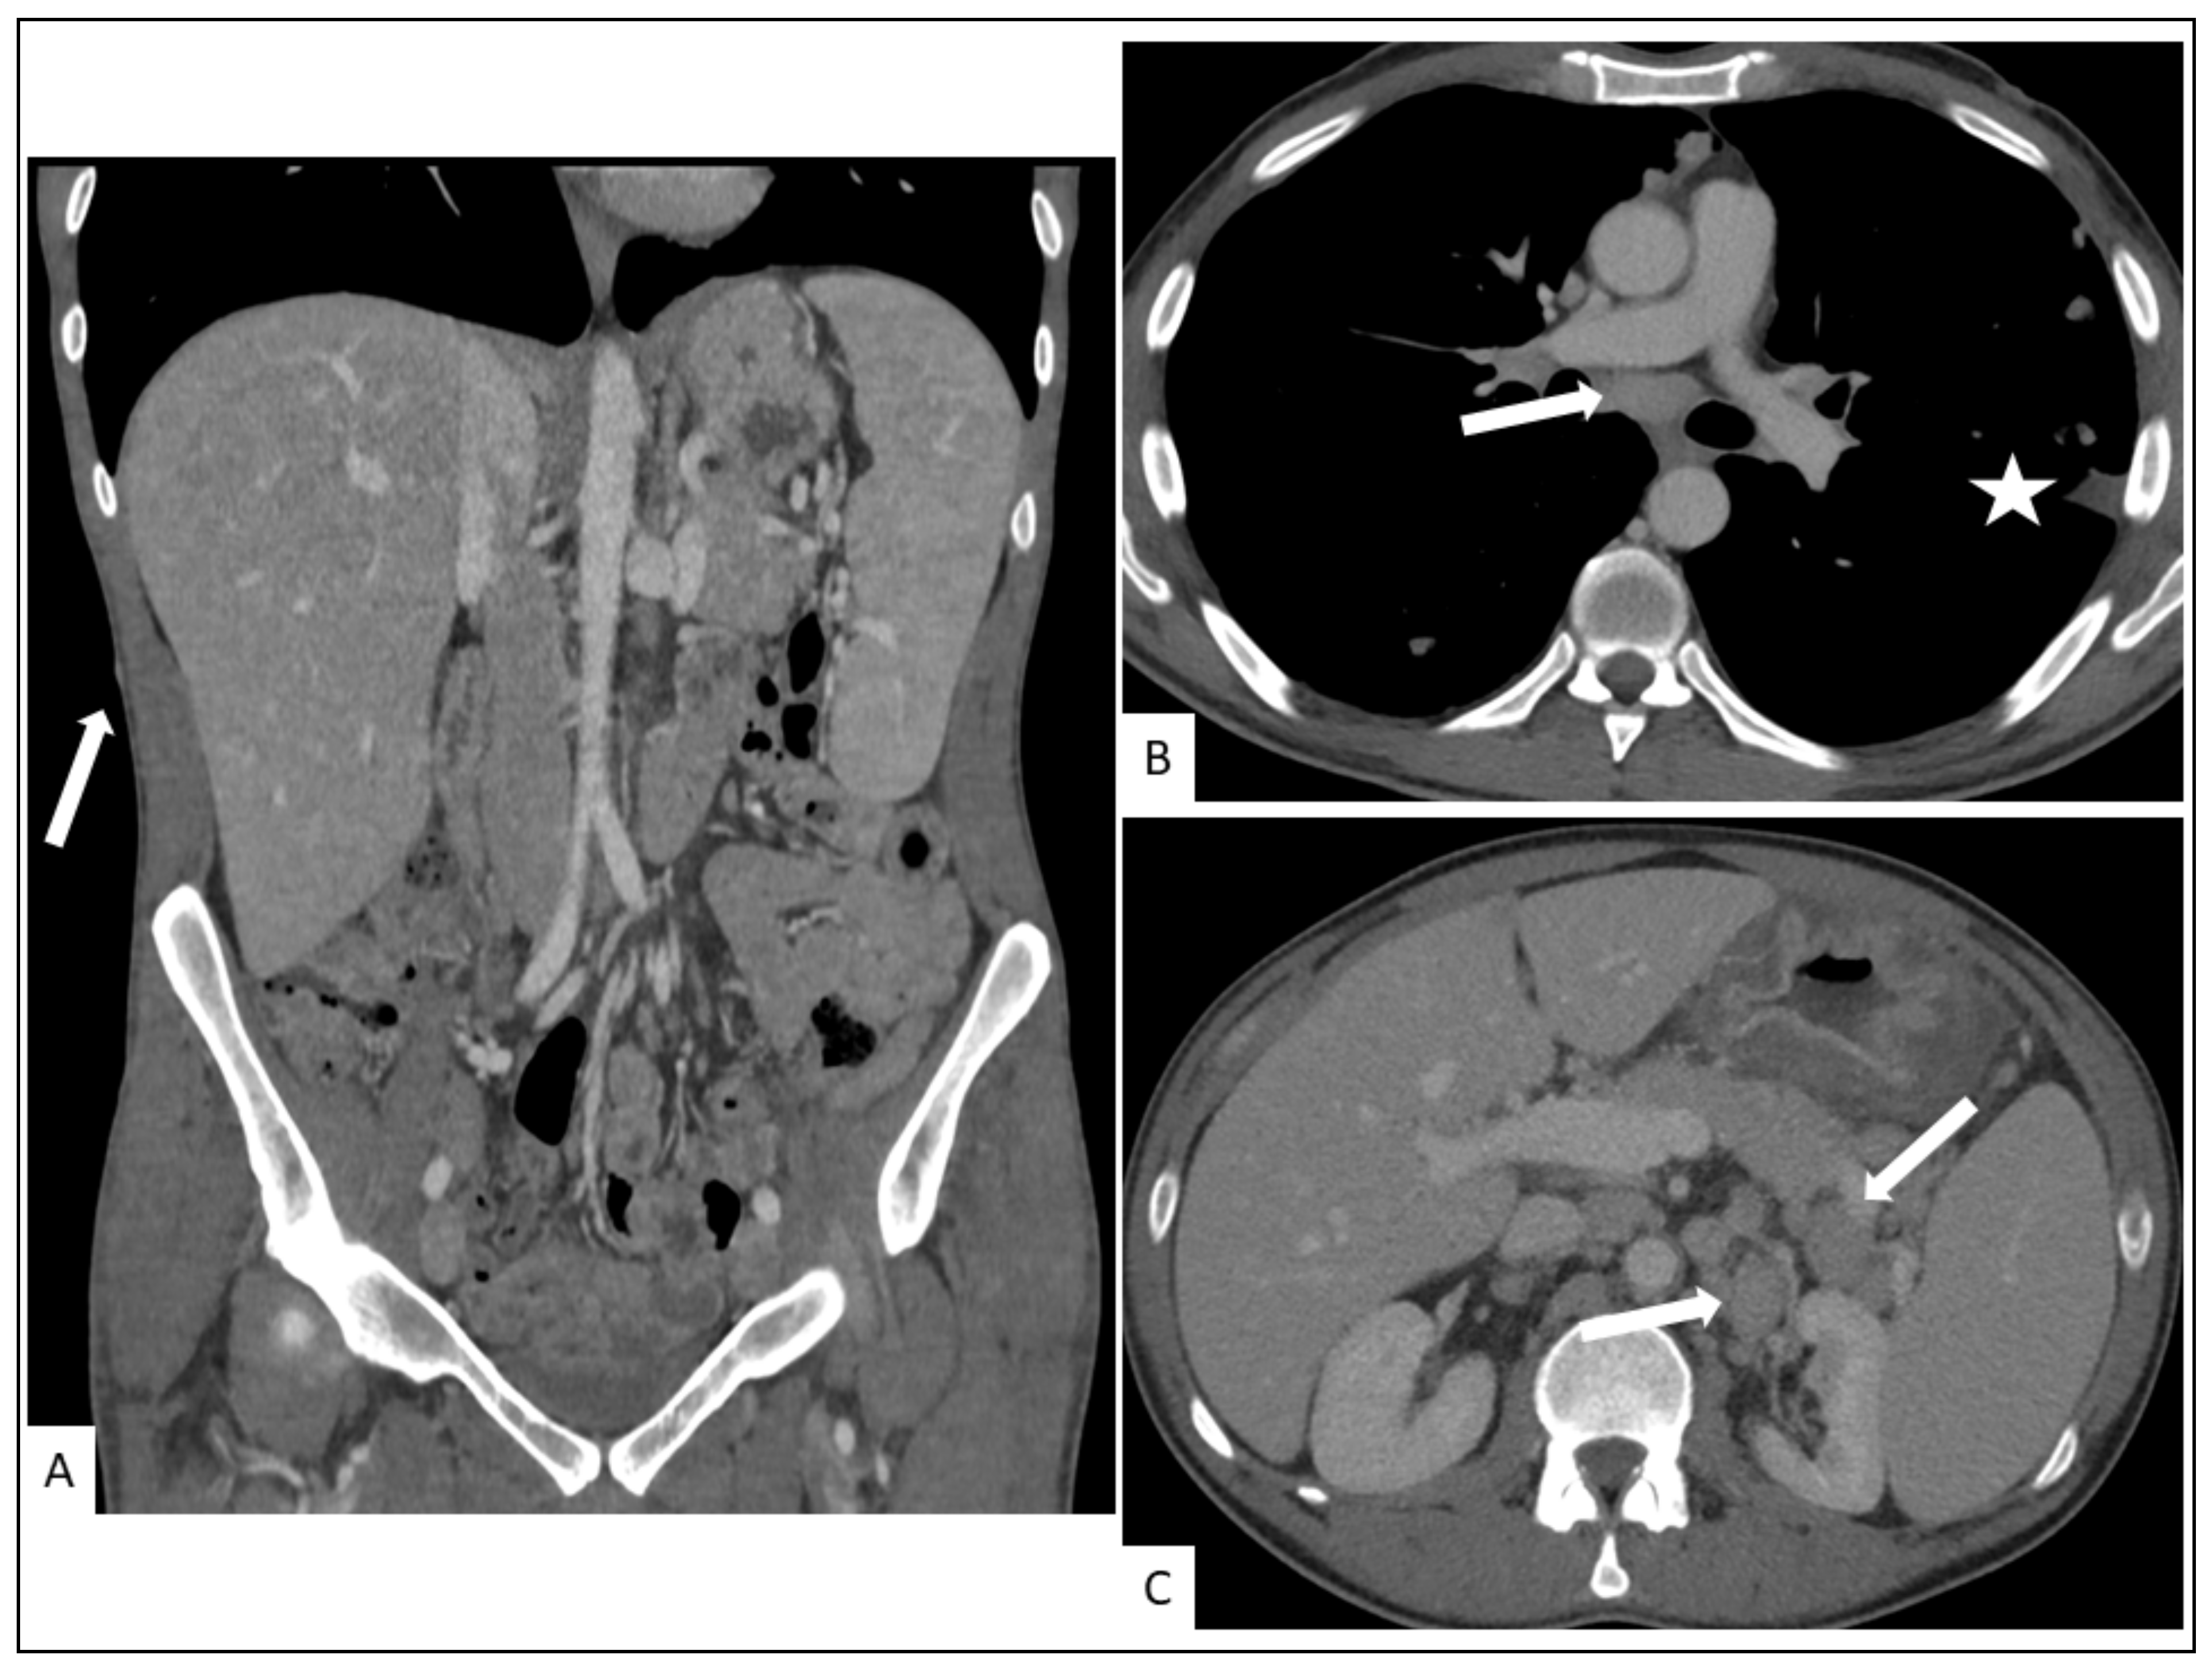

5. Radiological Presentation

5.1. Pulmonary KS

5.2. Hepato-Splenic KS

5.3. Other Visceral Involvement